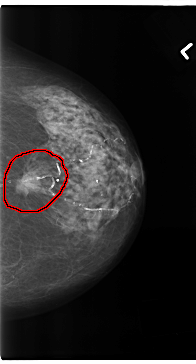

ics_version 1.0 filename C-0196-1 DATE_OF_STUDY 16 9 1996 PATIENT_AGE 83 FILM FILM_TYPE REGULAR DENSITY 2 DATE_DIGITIZED 26 3 1998 DIGITIZER LUMISYS LASER SEQUENCE LEFT_CC LINES 4728 PIXELS_PER_LINE 2536 BITS_PER_PIXEL 12 RESOLUTION 50 OVERLAY LEFT_MLO LINES 4736 PIXELS_PER_LINE 2712 BITS_PER_PIXEL 12 RESOLUTION 50 OVERLAY RIGHT_CC LINES 4616 PIXELS_PER_LINE 2824 BITS_PER_PIXEL 12 RESOLUTION 50 NON_OVERLAY RIGHT_MLO LINES 4672 PIXELS_PER_LINE 2712 BITS_PER_PIXEL 12 RESOLUTION 50 NON_OVERLAY |

FILE: C_0196_1.LEFT_MLO.OVERLAY TOTAL_ABNORMALITIES 1 ABNORMALITY 1 LESION_TYPE MASS SHAPE OVAL MARGINS SPICULATED ASSESSMENT 5 SUBTLETY 5 PATHOLOGY MALIGNANT TOTAL_OUTLINES 1 BOUNDARY |